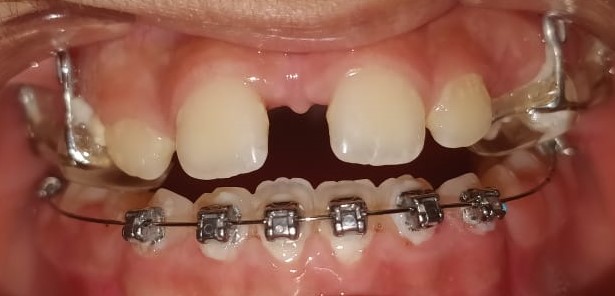

37) Jad – Upper and lower crowding and both laterals are palatally placed. – Upper treatment is completed.